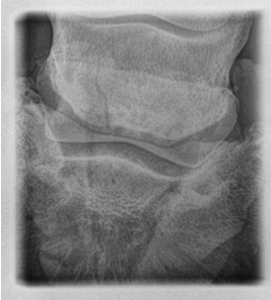

• what view is this?

dorsoproximal Palmarodistal 60o oblique